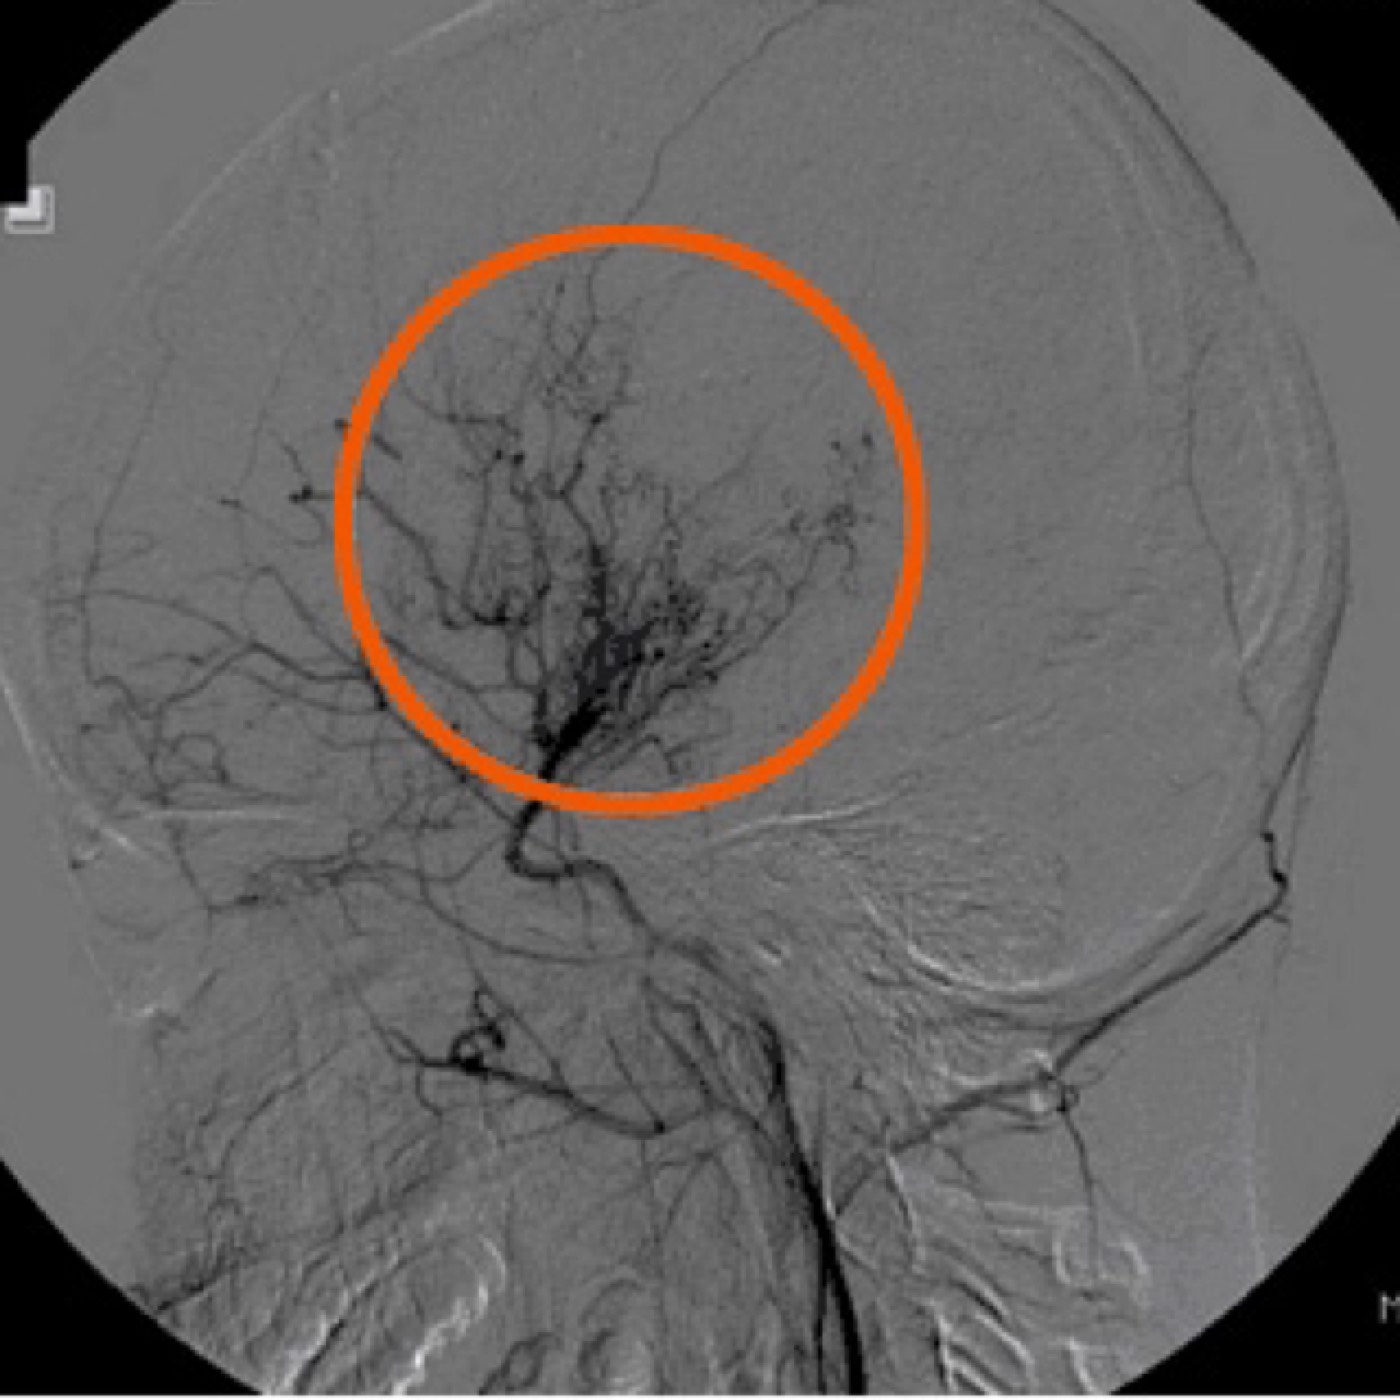

Contributor: Aaron Lessen, MD Educational Pearls: Traumatic Brain Injuries are a frequent complaint in the Emergency Department and have increased in recent years. The American Association for Surgery of Trauma (AAST) has created Brain Injury Guidelines (BIG), in an attempt to categorize brain injuries and the level of treatment they require. They are… BIG 1 Normal neuro exam Not intoxicated Not on anticoagulation or antiplatelet medications Minimal findings on head CT No fracture Maximum of "trace" subarachnoid hemorrhage No intraventricular hemorrhage Monitor for 6 hours No need to repeat the head CT No need to consult neurosurgery BIG 2 Normal neuro exam Not on anticoagulation or antiplatelet medications Any of the following Intoxicated Slightly more findings on head CT Non-displaced skull fracture 4-8 mm bleed (subdural, epidural, intraparenchymal (max two locations)) Maximum of "localized" subarachnoid hemorrhage No intraventricular hemorrhage Hospitalize No need to transfer No need to repeat the head CT No need to consult neurosurgery BIG 3 Abnormal neuro exam On anticoagulation or antiplatelet medications Intoxicated Significant findings on head CT Displaced skull fracture >8 mm bleed (subdural, epidural, intraparenchymal (or more than 2 locations)) "Scattered" subarachnoid hemorrhage Intraventricular hemorrhage Full treatment, admission to trauma center, neurosurgery evaluation References Joseph B, Friese RS, Sadoun M, Aziz H, Kulvatunyou N, Pandit V, Wynne J, Tang A, O'Keeffe T, Rhee P. The BIG (brain injury guidelines) project: defining the management of traumatic brain injury by acute care surgeons. J Trauma Acute Care Surg. 2014 Apr;76(4):965-9. doi: 10.1097/TA.0000000000000161. PMID: 24662858. Joseph B, Obaid O, Dultz L, Black G, Campbell M, Berndtson AE, Costantini T, Kerwin A, Skarupa D, Burruss S, Delgado L, Gomez M, Mederos DR, Winfield R, Cullinane D; AAST BIG Multi-institutional Study Group. Validating the Brain Injury Guidelines: Results of an American Association for the Surgery of Trauma prospective multi-institutional trial. J Trauma Acute Care Surg. 2022 Aug 1;93(2):157-165. doi: 10.1097/TA.0000000000003554. Epub 2022 Mar 28. PMID: 35343931. Summarized by Jeffrey Olson, MS4 | Edited by Jeffrey Olson and Jorge Chalit, OMS4 Donate: https://emergencymedicalminute.org/donate/